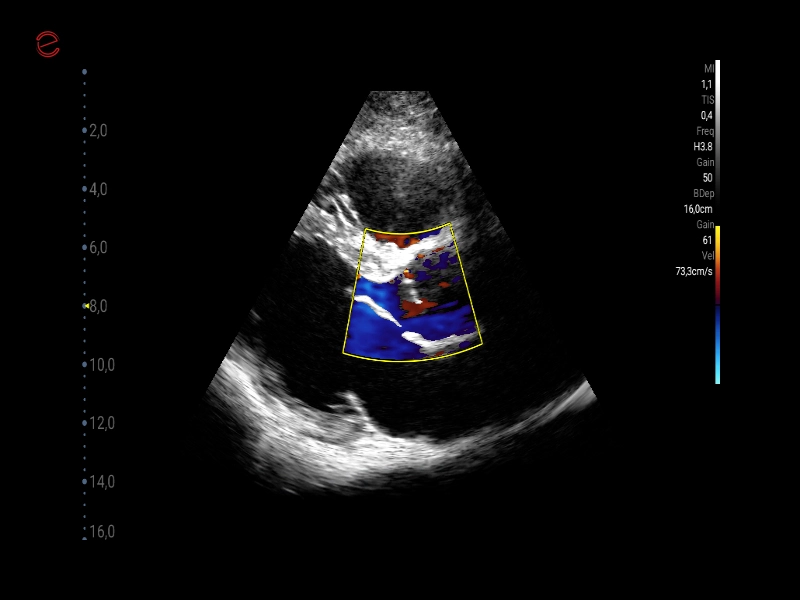

MyLab™C30 - CFM - TR

MyLab™C30 - CFM - TR

MyLab™C30 - CFM - 3CH

MyLab™C30 - CFM - 3CH